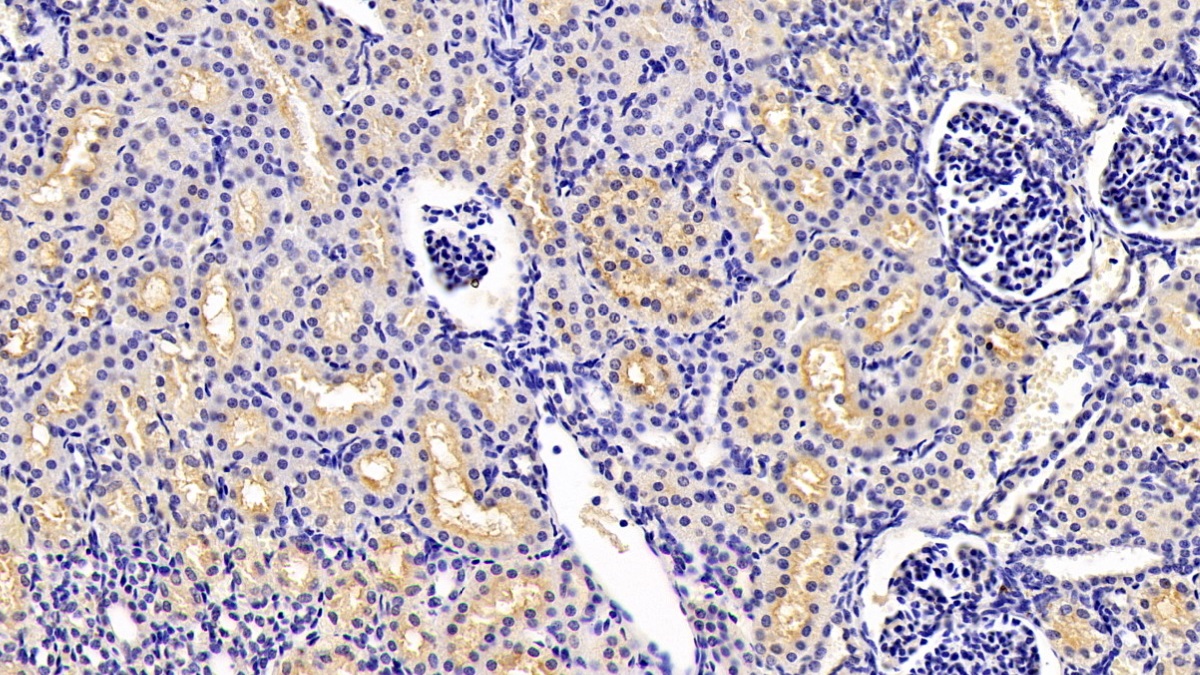

| Applications | WB; IHC; ICC; IP. |

| Product Synonyms | Anthrax Toxin Receptor 2 (ANTXR2) |

| Alternative Names | CMG-2; CMG2; ISH; JHF; Capillary Morphogenesis Protein 2 |

| Immunogen (Antigen) | Anthrax Toxin Receptor 2 |

Anthrax Toxin Receptor 2 (ANTXR2) Human Monoclonal Antibody